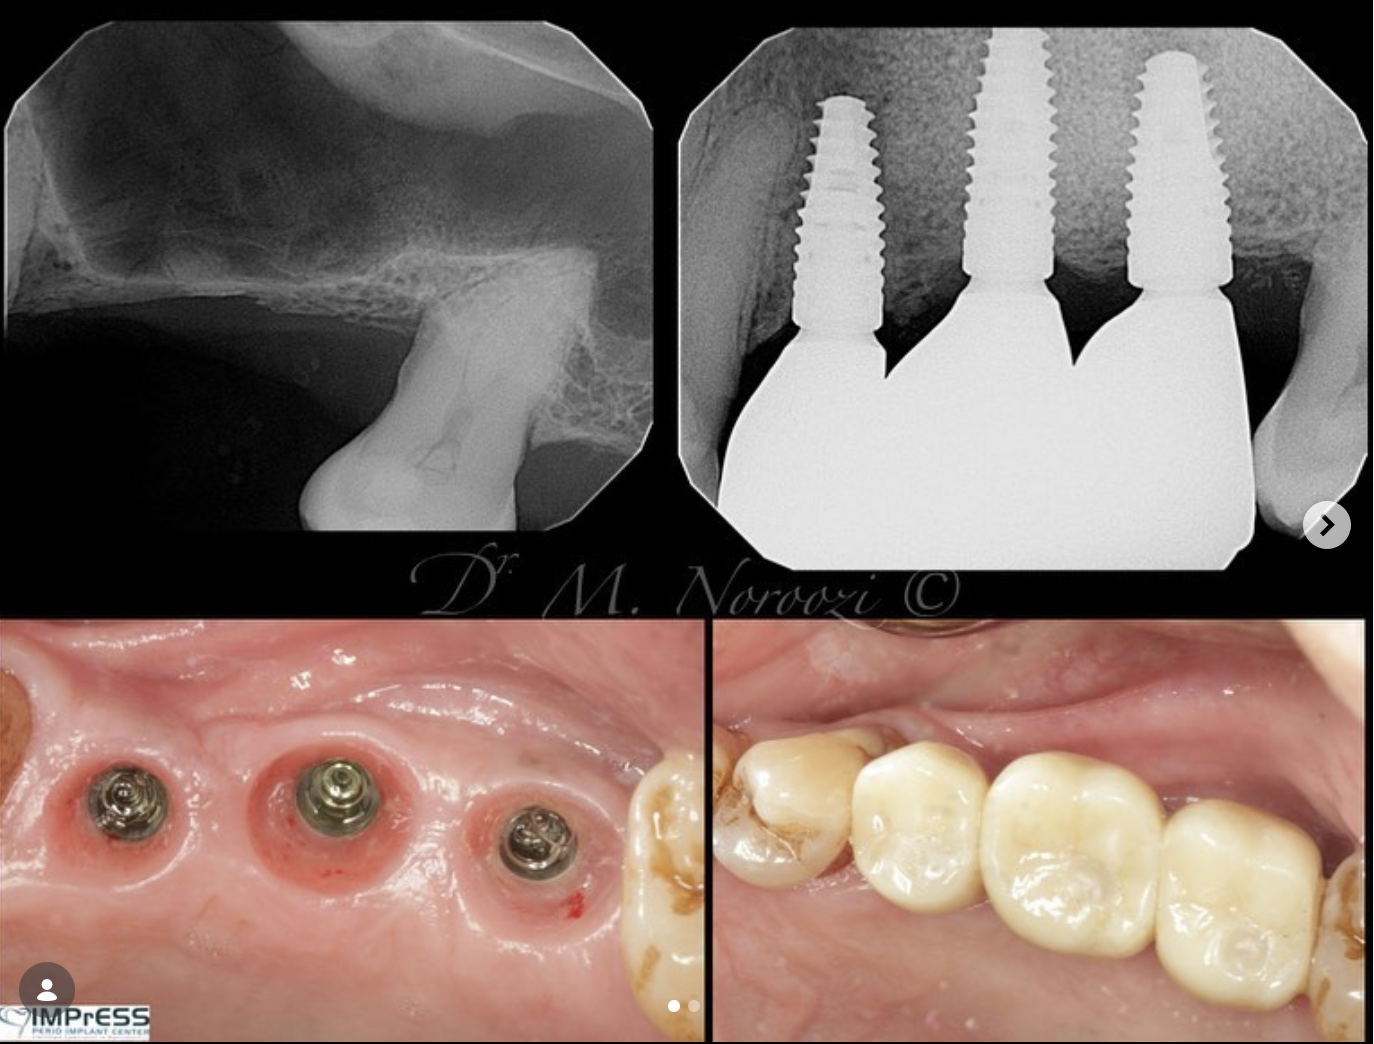

Before & Afters of Dental Implant Patients

Complete Dental Implant Cases Gallery

• When replacing several teeth or all of your teeth, a fixed bridge is anchored to your dental implants. A bridge is a dental restoration that replaces one or more missing teeth by spanning an area that has no teeth. The bridge is held firmly in place by dental implants on each side of the missing tooth or teeth.

What to do if my dental implants have failed?

If you have dental implants from another practice that are failing or have failed we can help! Dr. Noroozi and IMPrESS team are experts in treating implant complications. Call our expert staff to schedule a consultation where our periodontist will examine the implants and discuss with you the options for repair or replacement.

Dental implant treatment is sometimes a team effort between your periodontist and a restorative dentist.  Dr. Noroozi  at IMPrESS Perio Implant Center located in Burnaby BC performs the actual implant surgery, initial tooth extractions, and bone and gum grafting if necessary.  The restorative dentist (your dentist) or our specialists (if you do not have a dentist) will fit and make the permanent prosthesis. Your dentist or our specialists will also make any temporary prosthesis needed during the implant process.

General Disclaimer: The results in the photographs are examples only and do not imply any certainty of the result of a procedure, and all outcomes are subject to the circumstances of the individual patient.